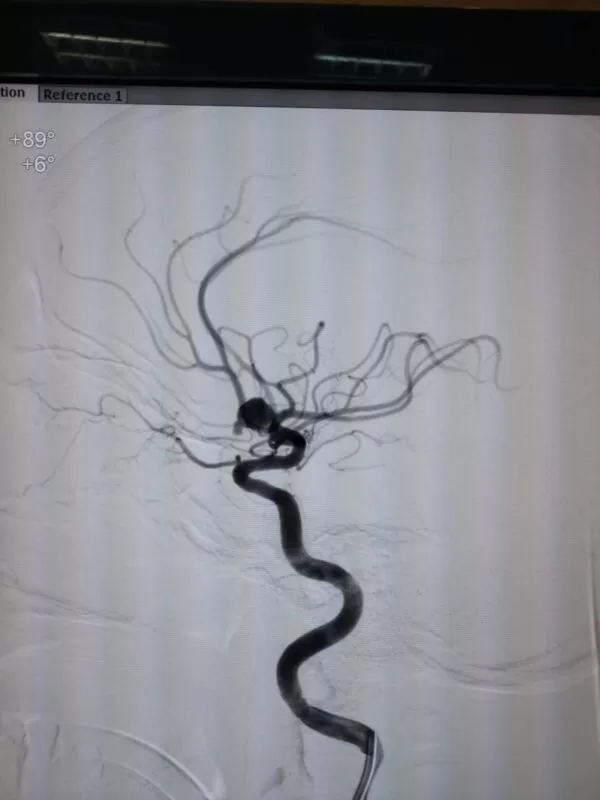

- القسطرة المخية التشخيصية

القسطرة المخية التشخيصية (قسطرة المخ الاستكشافية)

دكتور أحمد الغيطي يعد القسطرة المخية هي المرجع الرئيسي للكشف عن أي اضطراب في الشرايين والأوردة المخية.

يجري دكتور أحمد الغيطي القسطرة المخية تحت تأثير التخدير الموضعي لدى معظم الحالات وفي المقابل قد يتم الإجراء تحت تأثير التخدير الكامل في حالة وجود اضطراب في وعي المريض.

يعتمد هذا الإجراء على إدخال أنبوبة رفيعة للغاية عبر ثقب صغير في منطقة أعلى الفخذ حيث تعبر خلال الشريان الأورطى ومنه إلى شرايين المخ ويقوم د\كتور أحمد الغيطي بإرشاد وتوجيه القسطرة التشخيصية أثناء هذه الخطوات بالأشعة السينية.